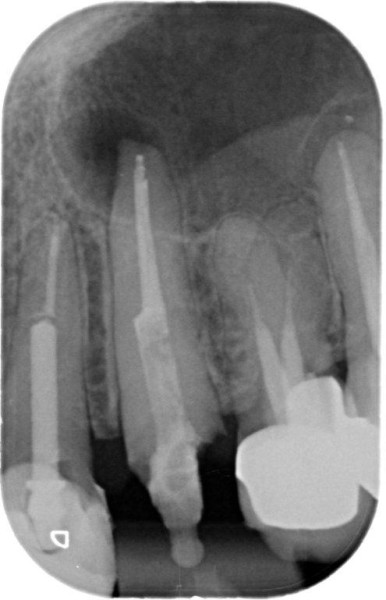

Molar retreatment

Re-treatments are more difficult than primary root canal work as the filling material has to be removed and any errors in the previous treatment corrected where possible.